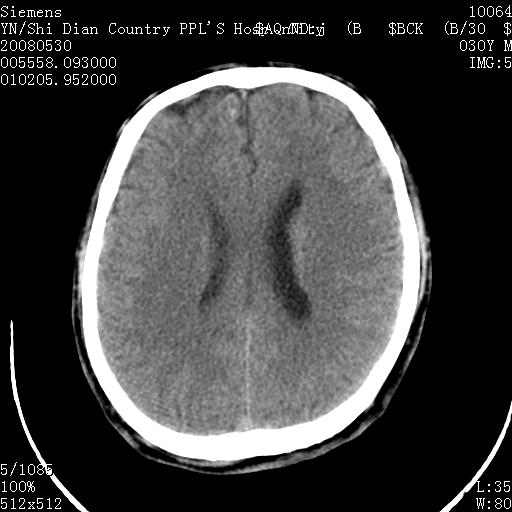

以下是引用pujunzhi在2008-7-10 13:06:00的发言:[br]透明间隔腔

以下是引用随光逐影在2008-7-10 15:19:00的发言:[br]1)考虑左侧尾状核钙化。2)透间隔间腔与vergae腔并存。

以下是引用卜一在2008-7-10 16:43:00的发言:[br]1)考虑左侧尾状核钙化。2)透间隔间腔形成。支持!